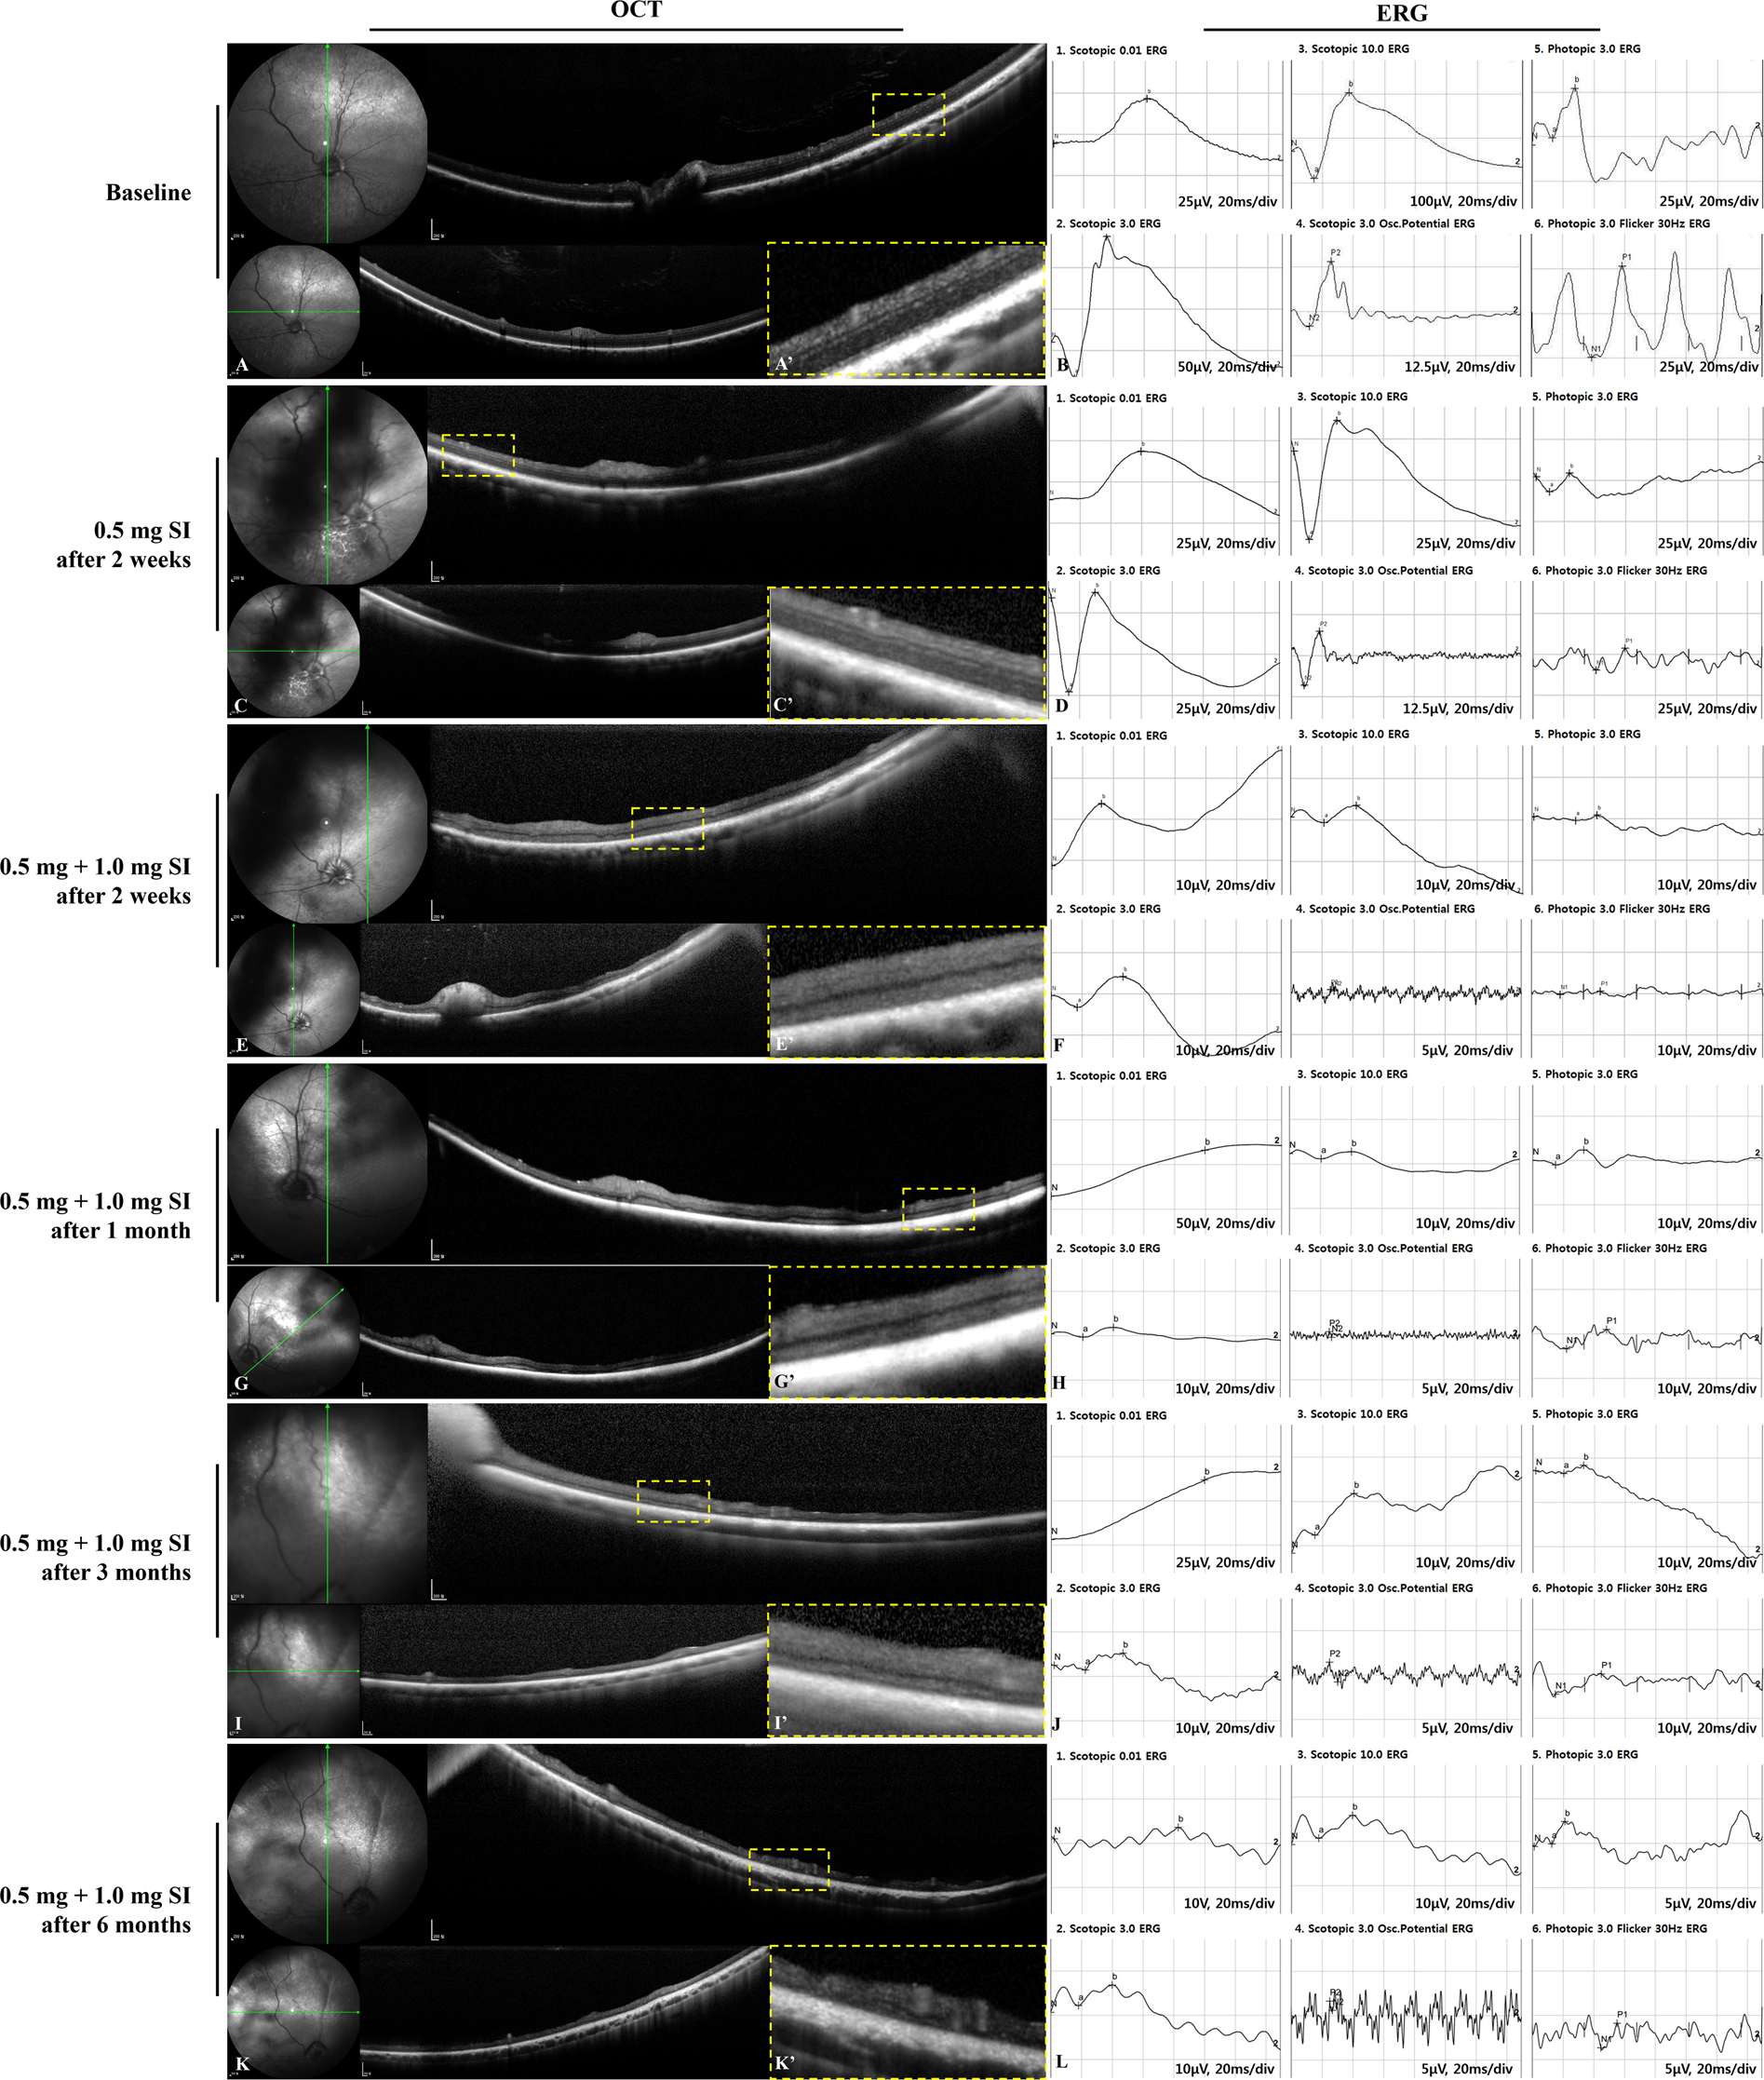

Vol 40 - n1 - p. Treatment of retinal rears and lattice degenerations in fellow eyes in high risk patients suffering retinal. Serial horizontal optical coherence tomography OCT scans after successful closure of macular hole after surgery.

Morphologic And Electrophysiologic Findings Of Retinal Degeneration After Intravitreal Sodium Iodate Injection Following Vitrectomy In Canines Scientific Reports